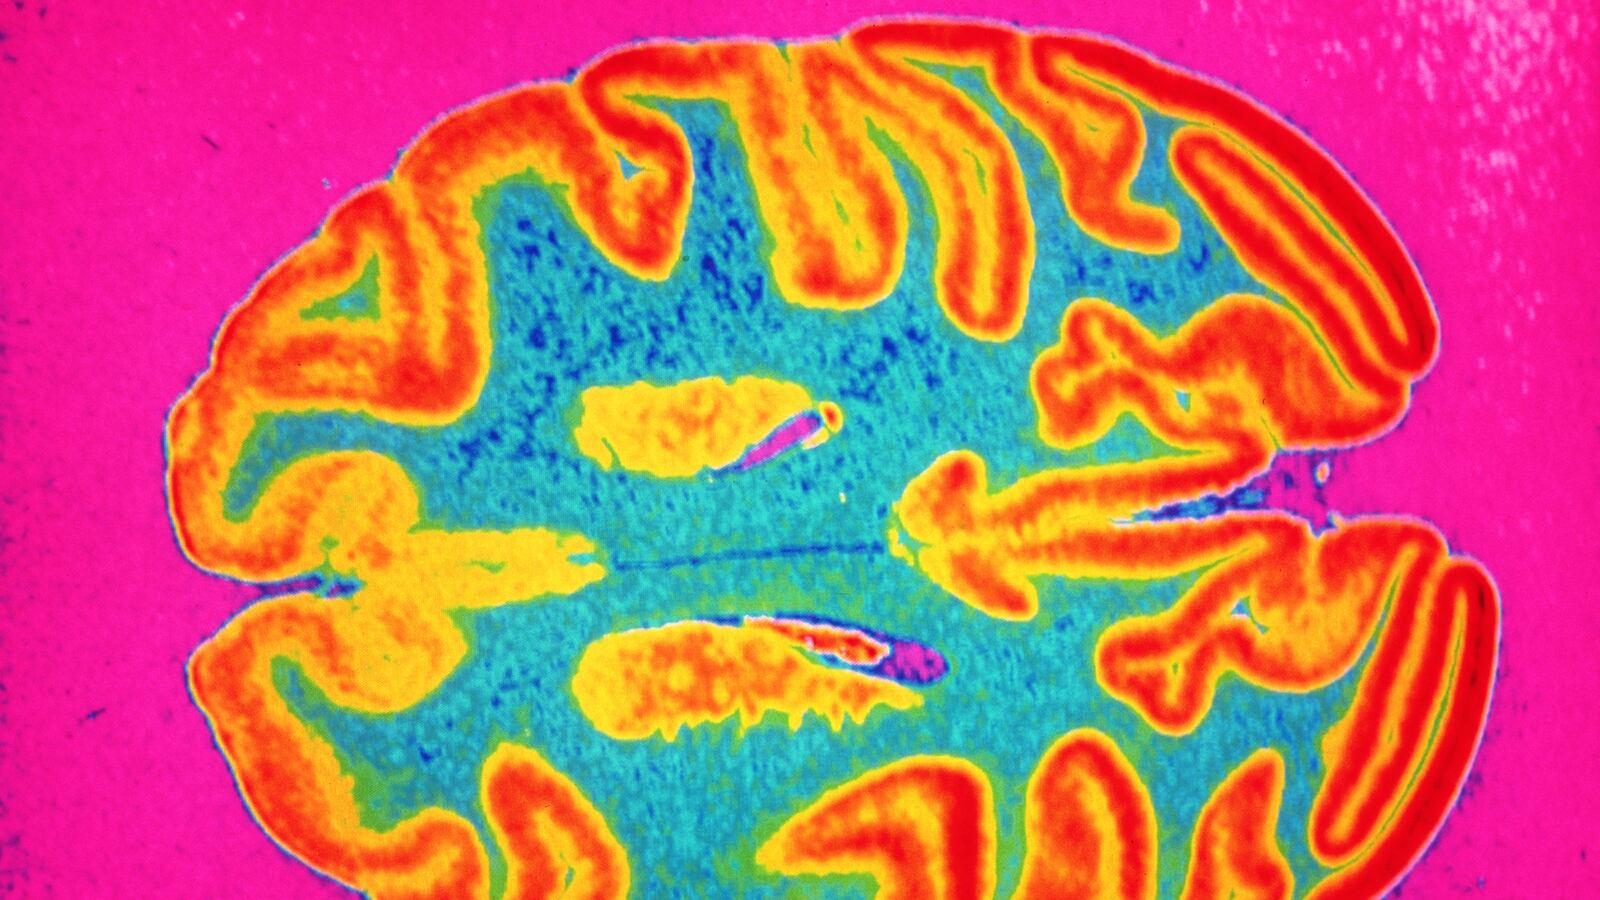

Six months ago I was discovered to have the tumor Glioblastoma Multiforme living inside my skull. At the same time my new novel Nod was approaching publication in North America. As both the disease and my novel progressed I began to notice eerie similarities between the two, even down to the physical similarity between the eye on the book’s cover and an image of the tumor itself, with its vein-like tendrils spreading out across my brain.